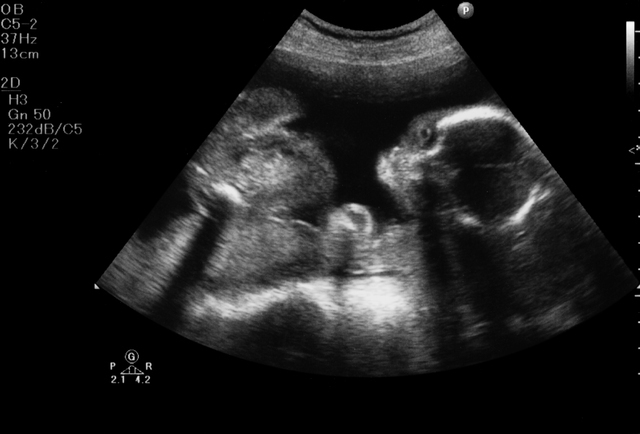

妊娠6ヶ月の胎児の大きさ、状態

反応|聴覚はほぼ完成、胎動の位置で逆子かどうかわかることも

この頃の赤ちゃんの聴覚はほぼ完成しており、ママの声や血液が流れる音、心臓の音などの他、お腹の外の大きな音も聞こえています。

お腹に話しかけたり、手でお腹をトントンと叩いたりすると、ポコポコとお腹を蹴って反応してくれる赤ちゃんもいるようです。

また、胎動を感じる位置によって逆子であるか分かるとも言われています。通常は、おへそよりも少し上の方で胎動を感じますが、逆子の場合、赤ちゃんの姿勢によって胎動を感じる位置が異なります。

逆子の場合、胃のすぐ下からおへその上あたり、肛門や膀胱、直腸の近く、お腹側の足の付け根のあたりで感じることが多いようです。